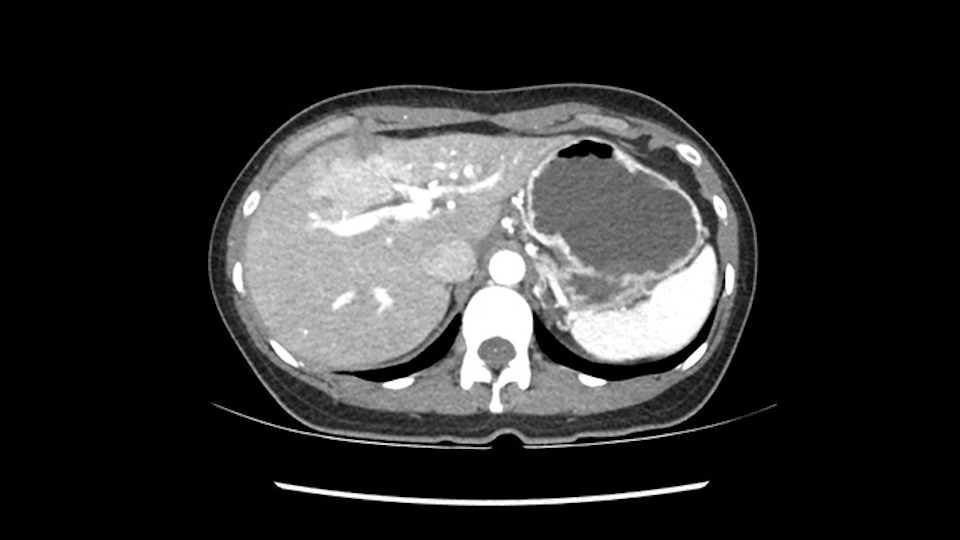

None of the parenchyma is affected and this tumor is very exophytic; like many Hepatitis B hepatomas; and otherwise is resectable with either a wedge resection part of Segment 2-3 or a formal left lateral segmentectomy.

As I review the CT scan, we have both arterial and venous phases, the tumor is obvious. But I’ll start by saying that the liver itself does not appear to be cirrhotic to my eye. It’s got a normal contour and allied to that, that I do not see evidence of portal hypertension. The spleen is normal, there’s no collateral vessels. The tumor itself, I measured maximally at about 11 centimetres in diameter and I’m told the alpha fetoprotein is very high (over 10000), which is entirely consistent with this being a solitary hepatocellular carcinoma that is very exophytic. It seems to emanate off the inferior margin of Segment 3 (because that’s the falciform). I’ll start by saying that this is not transplantable. The tumor exceeds our guidelines for transplantation, but it's likely resectable based on normal liver and no portal hypertension.

We note that the tumor is pushing on the gallbladder but I think that’s probably external for the most part. I think that’s extrahepatic. I believe that Segment 4b is probably free of tumor. I’d have to say that it's tempting, particularly looking at the coronals, to consider a very limited resection. Where you’d just chip it off the bottom of Segment 3 and do a limited Segment 3 resection. I’d be concerned about the oncologic margins. I believe that the best oncologic operation will be to take the left portal vein to get this. Certainly, she’s got plenty of liver and she’d be able to sacrifice Segments 2-3 of the left lobe of the liver. It’s not necessary to take too much of thus of Segment 4a. But once one takes the portal vein, that will be compromised. So I would do a left hemihepatectomy on this woman.

The tumor is so close to the falciform ligament, I had a question mark about the Segment 4b relation between segment 4b and segment 3. In a normal resection of segment 2 and 3, we would be keeping on the left side of the falciform ligament and start getting segment 3 and 2 portal pedicles but in here its getting so close. So oncologically, 4b should be checked during the OR.

What kind of procedure can we plan for this patient? It obviously has to be a left hemihepatectomy because most of the lesion is actually in Sg4. Can we do something which is less than a hemihepatectomy and just do only a segmental resection? The answer to that is that this vascular supply, if you are trying to ligate only the portal venous pedicle to the Segment 4, it is very close to the tumor and you will end up not having not a great margin as far as tumor resection is concerned so I would recommend a left hemihepatectomy and not just a partial or segmental resection. You can also see that it is crossing the falciform line and going on to Segment 2 and 3 so trying to do anything less than a left hemihepatectomy may not give the right kind of margins which we need for this tumor. Fortunately for us, the contours of the liver, which are very important to see in a Hepatitis B patient, there are no cirrhosis which I can see. The normal liver functions indicate that it's a well compensated Hepatitis B.

So in planning for this operation, as I look at the scans, I first visualize the arterial phase and I can see that there’s are a lot of big feeding arteries to this large tumor. Likely all the right side vessels feeding the right side of the liver: right hepatic artery and likely the Segment 4 artery are spared from the tumor. It’s likely the left hepatic artery is ramificating and giving feeding arteries to this tumor. It certainly looks like a large mass that its compressing other structures like the cava, the pancreas, the stomach; but I think there’s a plane and we can see that better in the venous phase. There’s a plane of separation between the gallbladder, the pancreas, the cava, that this tumor is abrupting but likely not invading. Usually, these masses actually don’t invade at that level and basically are pushing the tissues and once you open, you’re able to separate the tumor. Sometimes there’s some adhesions but you can actually separate and there’s usually no invasion.

The other thing I would do in this case is to certainly to assess the coronal phase as we can see in the coronal phase, this tumor looks like it's growing from Segment 3, and again I don’t think there’s involvement of the right side of the liver or even on Segment 4.